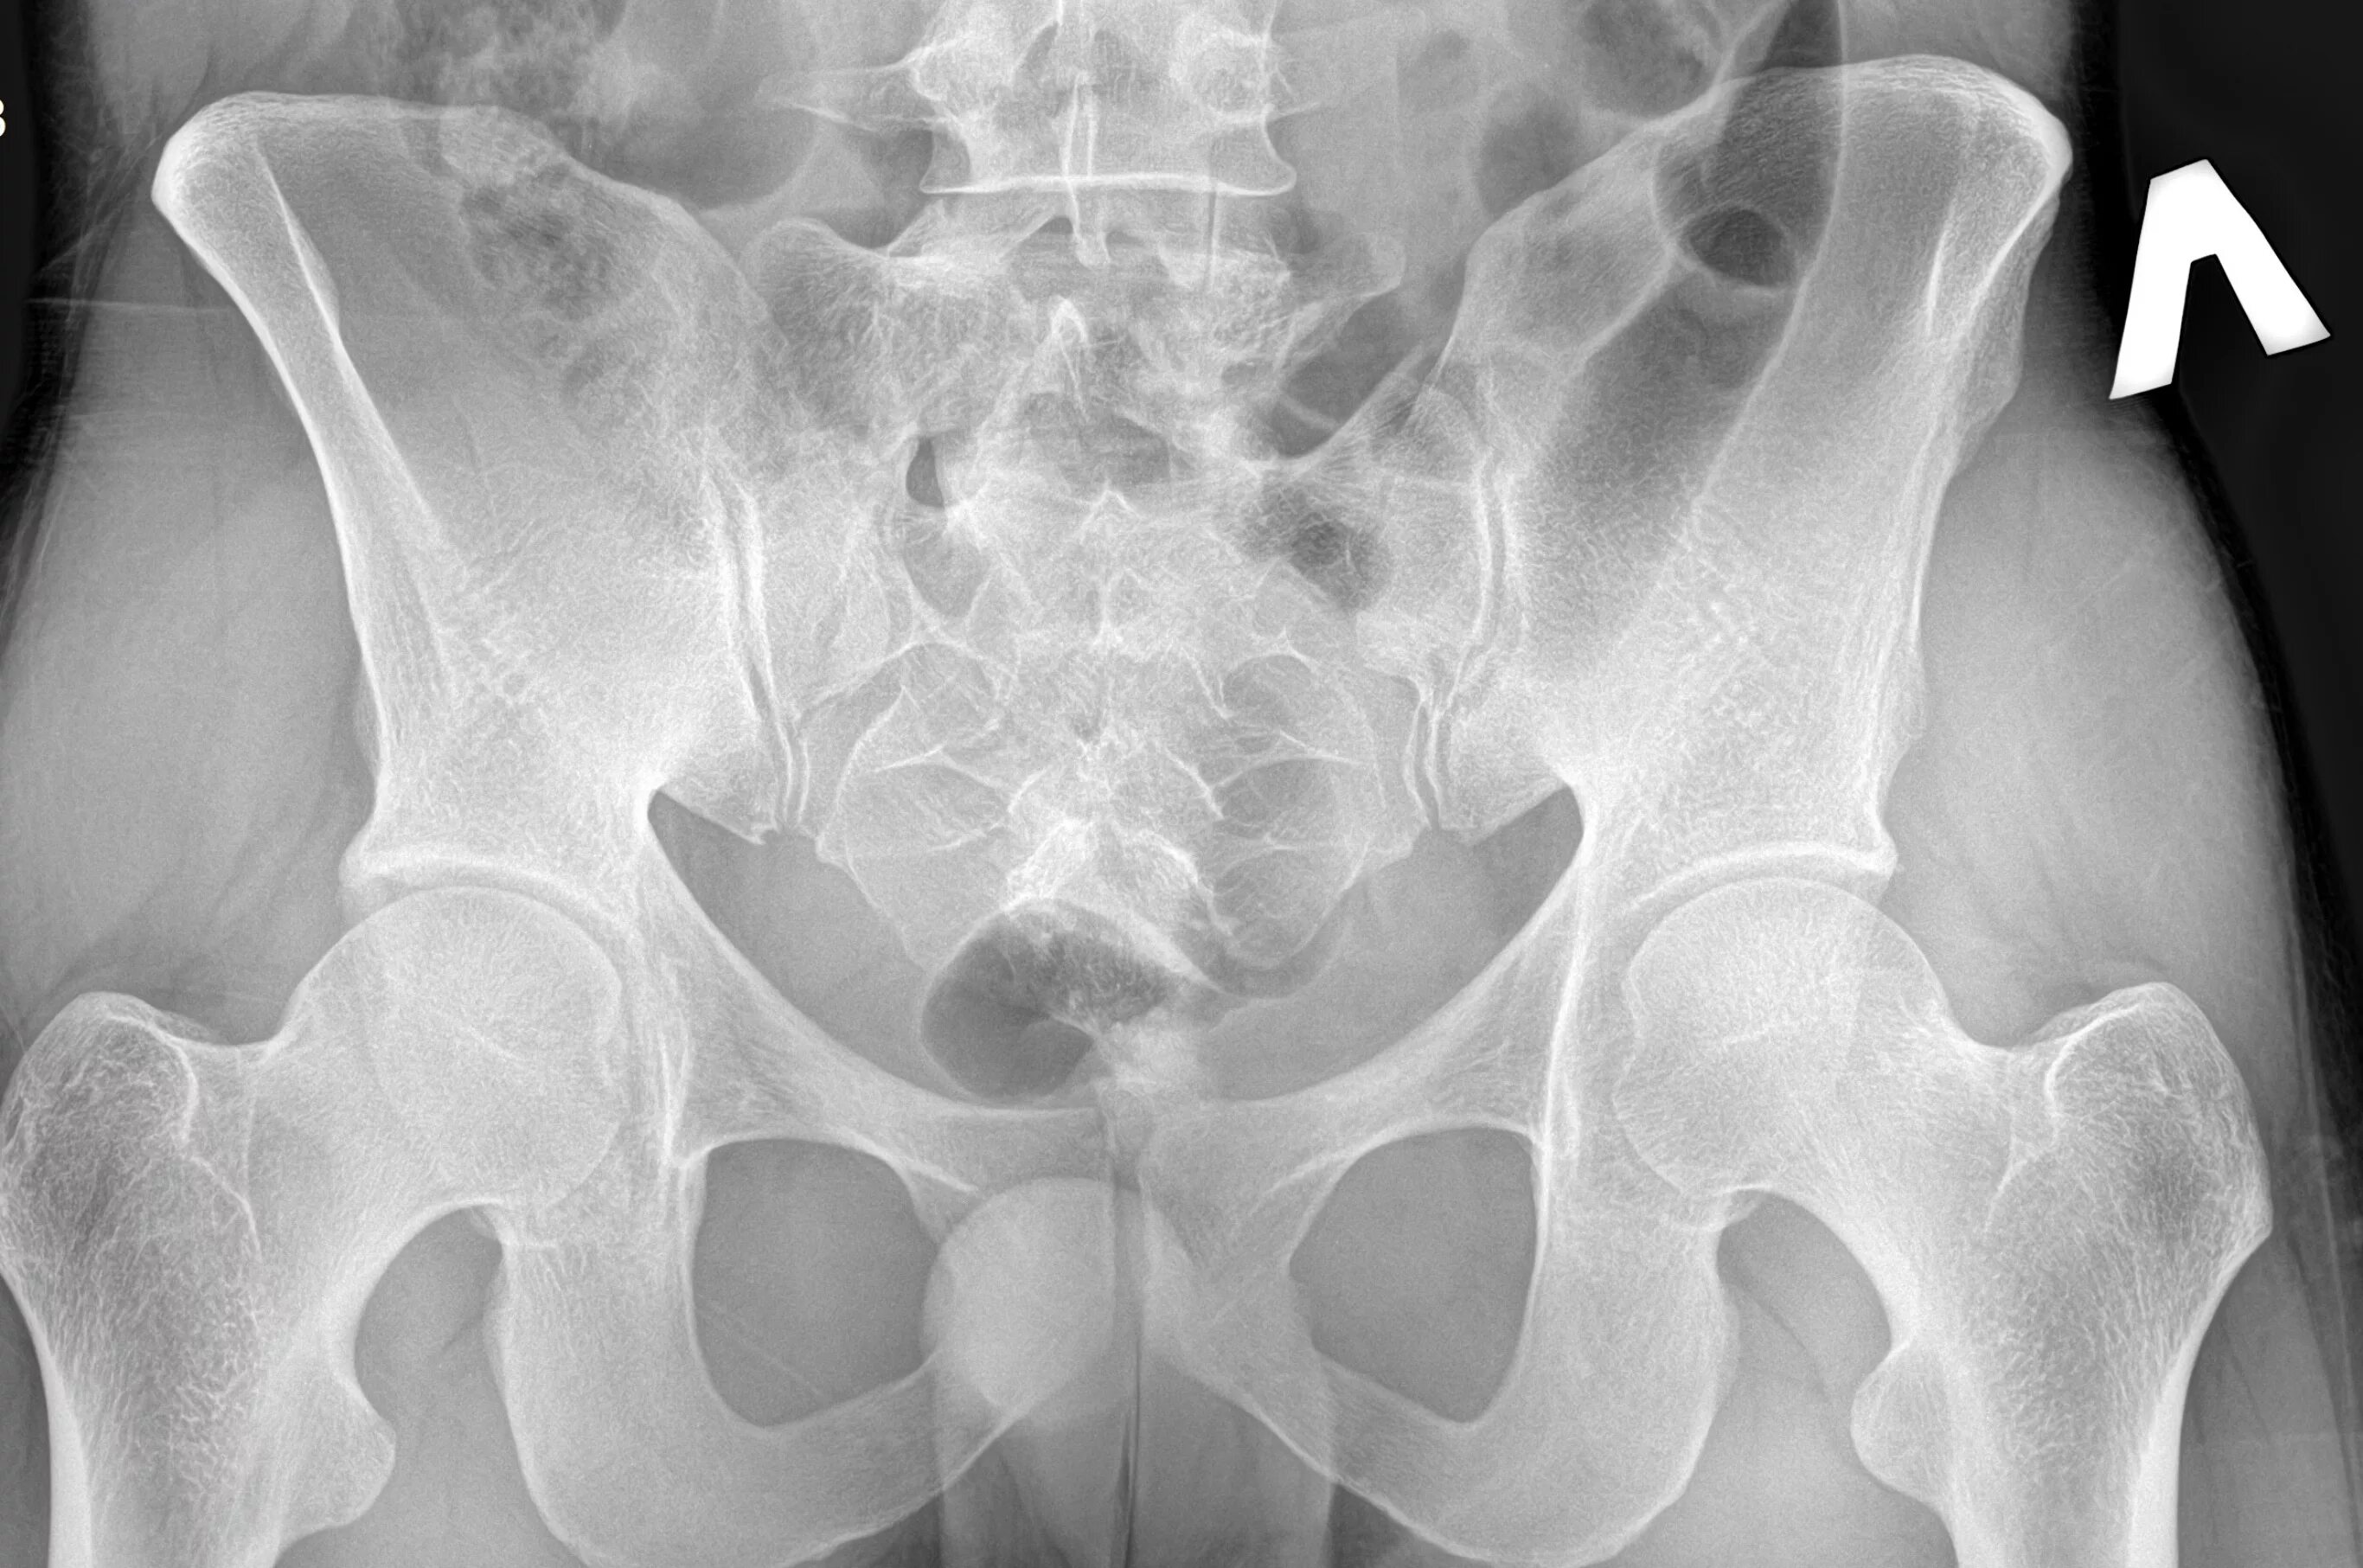

Снимок копчика